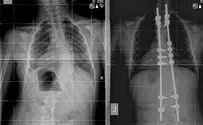

ילדה בת 8 נותחה השבוע במרכז הרפואי אסף הרופא בשיטת חדשה לטיפול בעקמת המצמצמת את הצורך בניתוחים חוזרים ונשנים.